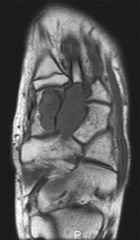

15 year old male with a left foot mass x >1yr.

It has recently grown in size and he has discomfort putting on hockey skates.